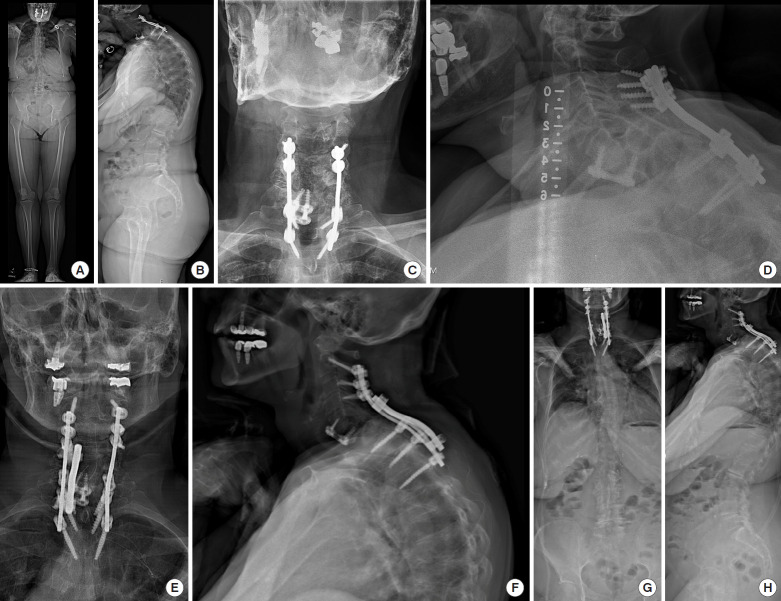

2. Case 2

This patient is a 70-year-old female with an acquired solitary kidney (living donor nephrectomy), esophagitis, and dysphagia who previously underwent a C5–7 anterior cervical discectomy and fusion at an outside hospital for facet fractures after a motor vehicle accident. One month later there was progressive spondylolisthesis of C6, necessitating a posterior cervical fusion from C4–T2 and a C5–7 laminectomy. Since that time she has developed progressive and persistent neck pain, bilateral arm pain, problems with balance, and difficulty holding her head up. Radiographs demonstrate lateral mass screw pull-out and a grade 4 spondylolisthesis at C6–7. Her exam is notable for 4/5 strength in the left triceps, hyperreflexia, poor tandem gait, and a positive Hoffman’s sign. Radiographic assessment reveals a CL of 17° and a T1S of 38°, representing a mismatch of 21°. The C2–7 SVA is 6.8 cm. Per the Ames-ISSG classification, she is a type C with the following modifiers: 1, 2, 2, 2, N/0/0/0. Per the CSRSEurope classification she is a type B, given that she has cervical kyphosis that creates a large C2–7 SVA and regional imbalance. Per the Kim-ISSG classification, she is a type I, given the inability of the CL to fully compensate for the given T1S (on standing and extension x-rays) due to the C6–7 spondylolisthesis. The patient underwent a revision C2-T3 posterior fusion and revision decompression with duralysis at C5–T1, and the deformity was corrected with bivector traction and posterior column osteotomies only. The postoperative CL improved to 26° and the C2–7 SVA improved to 3.7cm. See Fig. 7 for pre- and postoperative films.

Fig. 7.

Case example No. 2. (A) Preoperative anteroposterior (AP) EOS film, (B) preoperative lateral EOS film, (C) preoperative AP plain film, (D) preoperative lateral plain film, (E) postoperative AP plain film, (F) postoperative lateral plain film, (G) postoperative AP EOS film, (H) postoperative lateral EOS film.